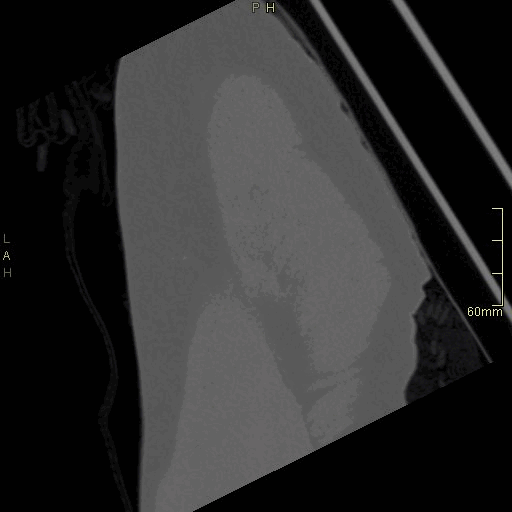

CT Hip Contrast- Soft tissue window (coronal)

CT Hip Contrast- Bone window (coronal)

CT Hip Non Contrast- Bone window (coronal)